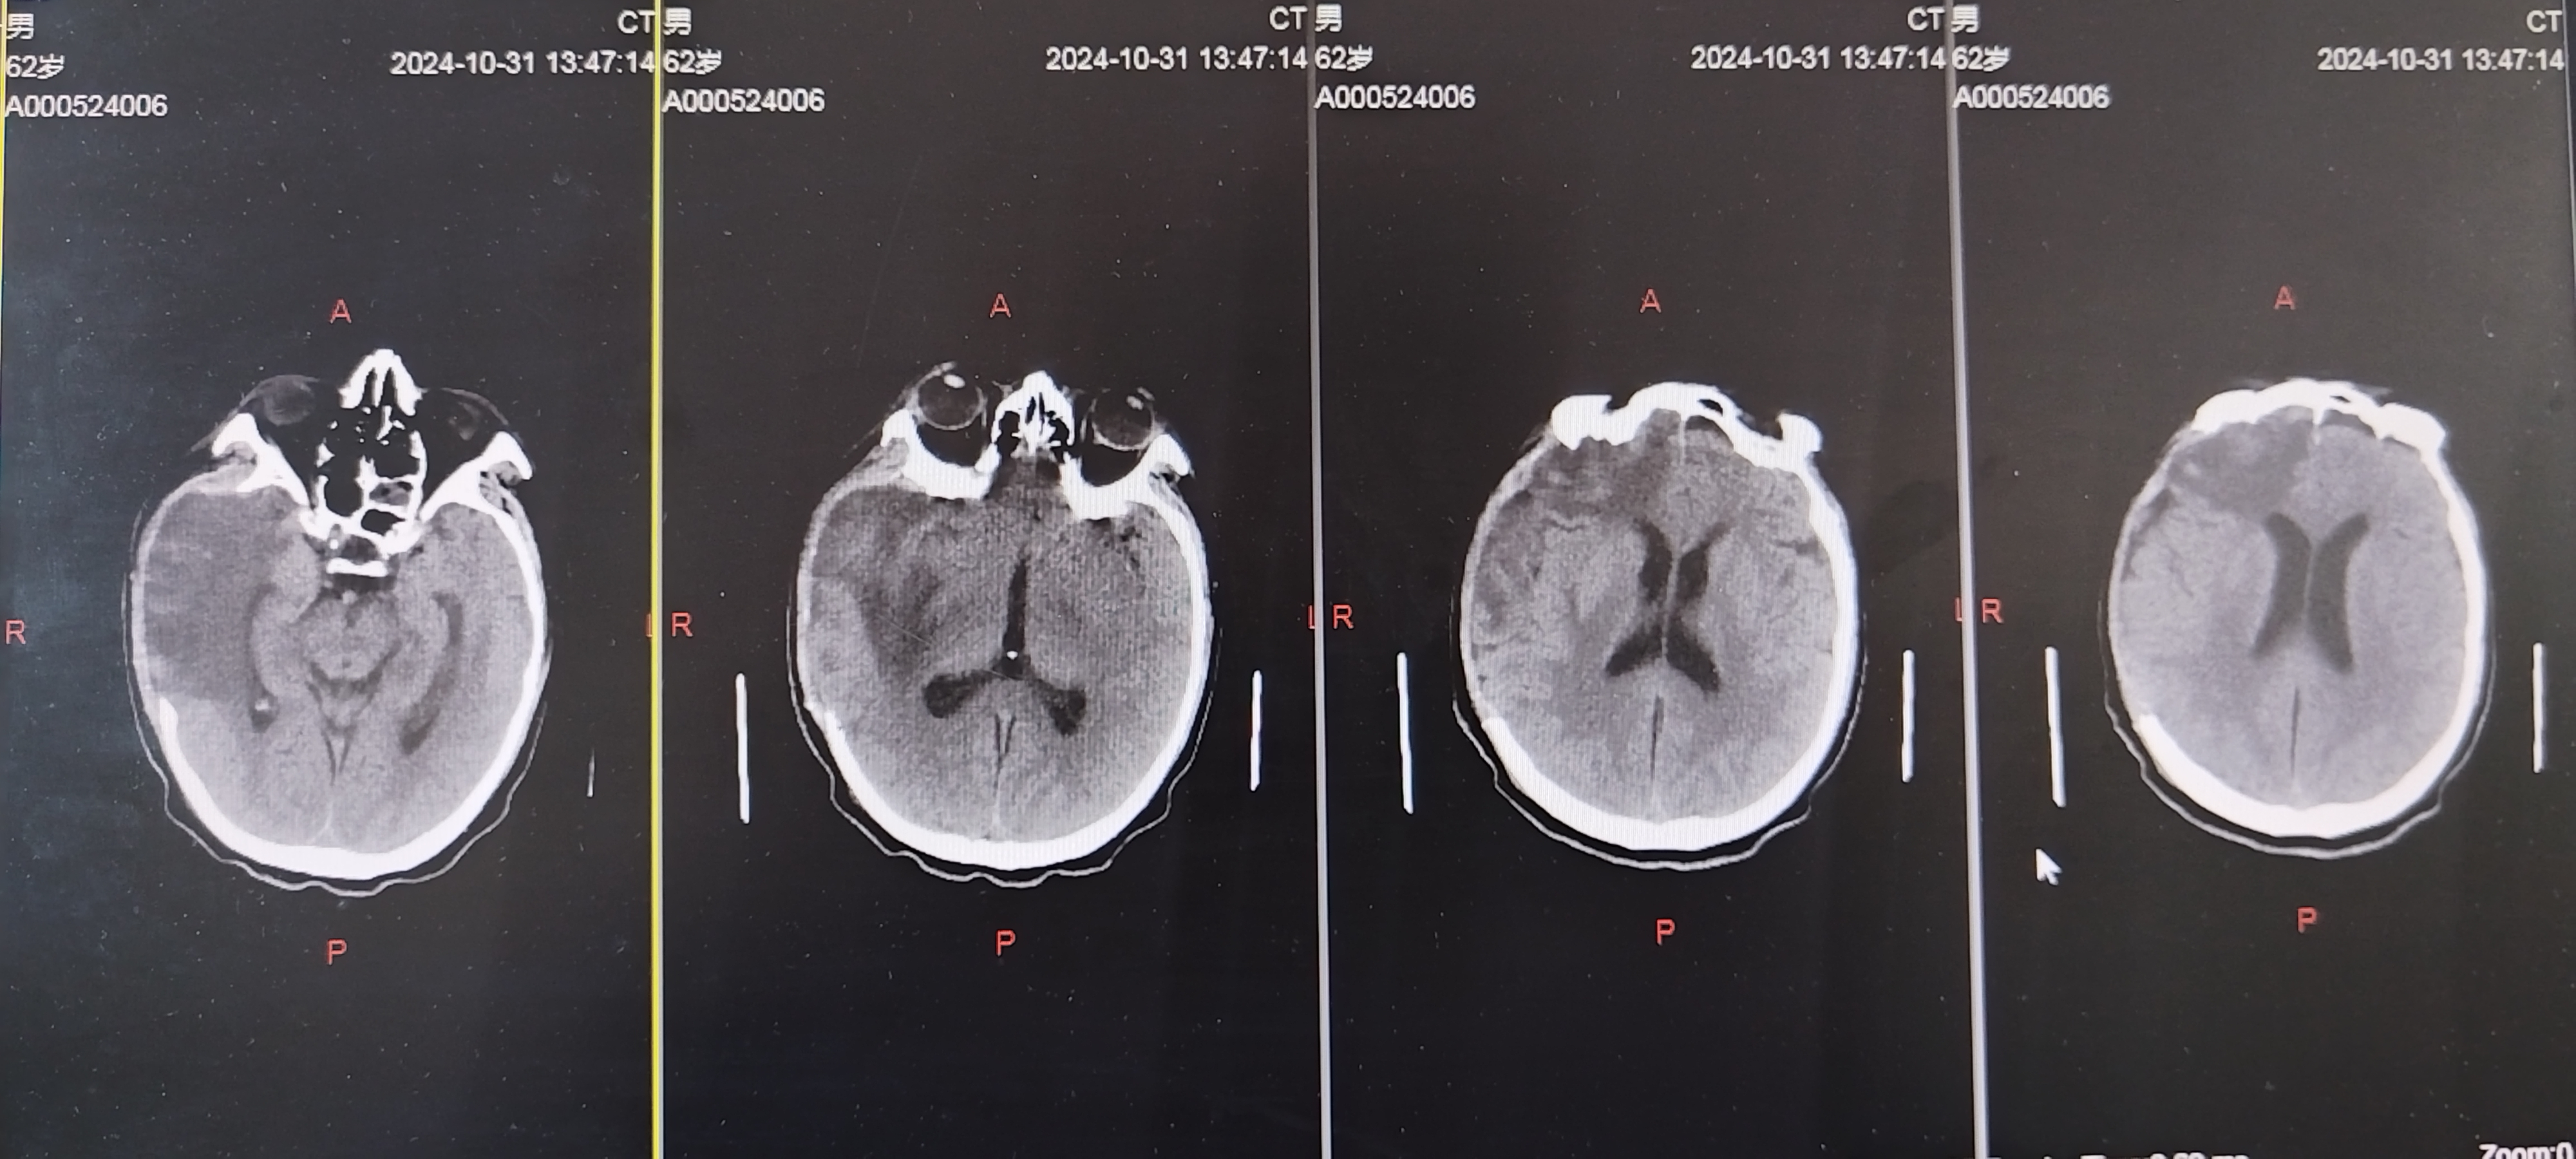

术后1周复查CT

术后3周复查CT